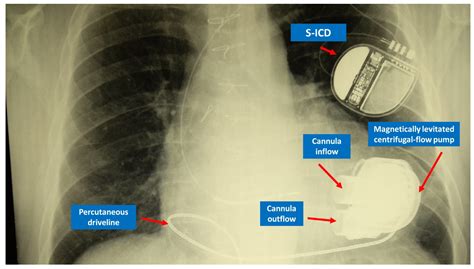

• Imaging studies such as X-rays, CT scans, or MRI to visualize the hyoid bone and surrounding structures.